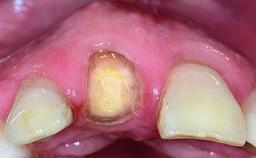

A 15-year-old male patient was referred to us by his pediatric dentist in June 2004 for evaluation of treatment options for his failing tooth 21. The patient had recently seen an endodontist for internal bleaching and been advised that there had been significant resorption and ankylosis. The patient’s mother was concerned because the tooth appeared shorter than the adjacent one. His past dental history was significant for trauma (September 2001), where the tooth had been avulsed and reimplanted. Teeth 11 and 21 had been endodontically treated.

| Bone Volume | Deficient horizontally, requiring prior grafting |

| Soft Tissue Contour and Volume | Significantly deficient |